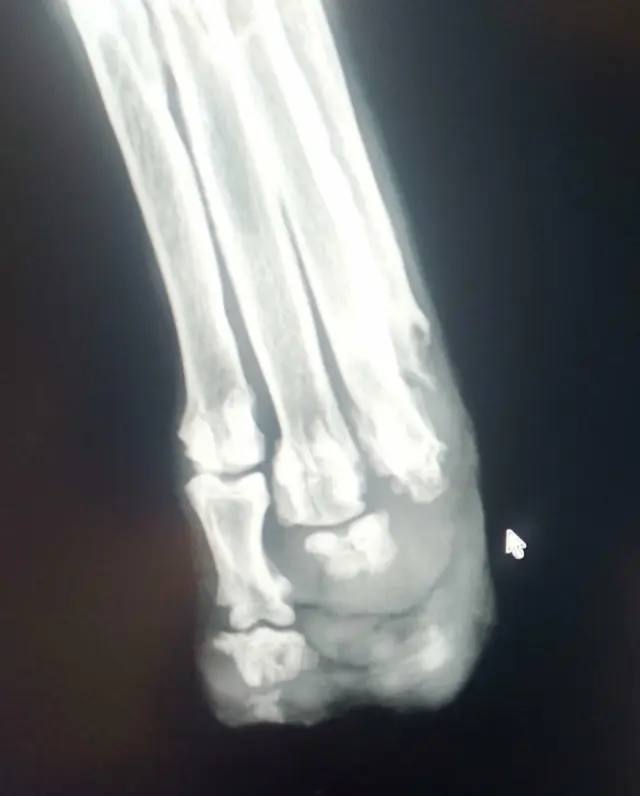

😭Bohužel, v tomto nejtěžším týdnu čekání na Foxe, zasáhla osudová rána i našeho druhého zachráněného Aspena – křížence borderkolie, kterému někdo v šesti měsících usekl zadní tlapku sekerou. Od března jsme léčili chronickou nehojící se ránu i laserem a je sice z venku již zhojená, ale teď znovu nesnesitelně trpí. Celá noha ho bolí, a jak nám potvrdilo RTG jde o lýzu (rozpad) kostí v důsledku traumatu a roztříštění, zánět a otok. Bolest je tak intenzivní, že se neovládá a při dotyku po nás už deset dní vyjíždí. Je to zoufalý křik jeho těla😭😭😭

V pátek absolvoval náročná vyšetření (RTG a po zjištění stavu nakonec i CT), aby ortopéd určil, v jaké výšce provést amputaci. Zda lze zachrání alespoň koleno a budeme řešit částečnou protézu nebo bohužel přistoupit k celkové amputaci, o což jsme však od března bojovali, aby k tomu nedošlo😭